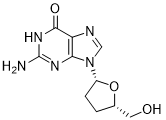

馬鞍山致研生物醫(yī)藥科技有限公司成立于馬鞍山市鄭浦港新區(qū)現(xiàn)代產(chǎn)業(yè)園。公司專(zhuān)注于生物小分子、醫(yī)藥中間體相關(guān)產(chǎn)品的研發(fā)和生產(chǎn),產(chǎn)品主要包括DNA亞磷酰胺單體、RNA亞磷酰胺單體、特殊單體以及按照客戶(hù)要求定制的RNA和DNA,并且公司提供定制合成等方面的研究服...

馬鞍山致研生物醫(yī)藥科技有限公司成立于馬鞍山市鄭浦港新區(qū)現(xiàn)代產(chǎn)業(yè)園。公司專(zhuān)注于生物小分子、醫(yī)藥中間體相關(guān)產(chǎn)品的研發(fā)和生產(chǎn),產(chǎn)品主要包括DNA亞磷酰胺單體、RNA亞磷酰胺單體、特殊單體以及按照客戶(hù)要求定制的RNA和DNA,并且公司提供定制合成等方面的研究服...